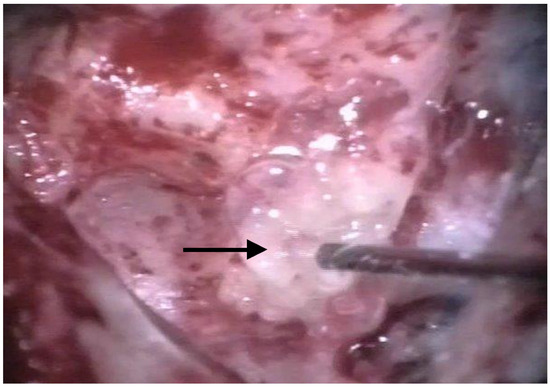

The patients were treated between August 2013 and October 2015 using the identical surgical technique of one-stage cochlear implantation and the occlusion of all three ipsilateral semi-circular canals. For cochlear implantation, a posterior tympanotomy and a round window approach were chosen [14]. Occlusion of the three semi-circular canals was performed before the implantation by reducing the drill speed to 10,000/min. The labyrinth was skeletonized to identify all semi-circular canals. The superior bony layer of the semi-circular canal was drilled down with a diamond burr (2.3 mm) until the endolymphatic duct shone through the last bony layer (blue lining) (Figure 1 and Figure 2). Leaving the endolymphatic duct intact, the temporalis fascia was pushed down in the canal. After sealing with fascia, the canal was filled with bone wax (Figure 3). The area of each canal was covered afterward with a muscle patch and bone pate. Finally, the sealing patch was secured with fibrin glue (Figure 4) [5,15].

Figure 4. In the last step, fibrin glue was used to seal the plug. The arrow points to the fibrin glue.